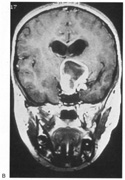

Fig. 15. Bilateral incomplete hemianopia. A 69-year-old man with decreased vision after prostate surgery. A. Fields show remaining central parafoveal vision with some sparing of inferior left quadrant. Note how the defect respects the vertical meridian. B. MRI shows bilateral medial occipital infarction, with sparing of the occipital poles, accounting for the macular-sparing bilaterally. (Courtesy of Dr. Lucia Vaina.)

Bilateral lesions of striate cortex are not rare. Focal midline lesions such as tumors or traumatic injury may affect both striate cortices concurrently, because the right and left striate cortices face each other on the medial occipital surface. The most common cause, however, is posterior circulation ischemia.57 This can affect both striate cortices either simultaneously or sequentially,57 because the right and left posterior cerebral arteries have a common origin from the basilar artery. Twenty-two percent of patients with a unilateral occipital infarction develop bilateral infarction over 3 years.58 Bilateral incomplete hemianopia is distinguished from bilateral optic nerve or ocular disease by the high congruity of the visual fields and step defects along the vertical meridian which indicate the hemifield nature of the visual loss (Fig. 15).57 Such steps are important to seek with a skilled perimetrist, but even so they can be difficult to demonstrate with bilateral hemiscotomata from occipital pole lesions.59 Bilateral quadrantanopias can occur,47,48 often in patients with prosopagnosia and achromatopsia for example, and may mimic the altitudinal defects of optic neuropathy.